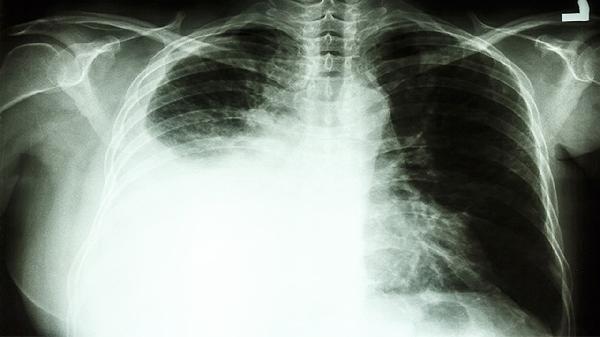

2、反流性食管炎:反流性食管炎胃酸反流刺激咽喉部,会出现喉咙里有痰咳不出来咽不下去。可以口服奥美拉唑、枸橼酸莫沙比利治疗。同时口服化痰药物盐酸氨溴索片治疗。

2.支气管炎:支气管炎主要原因为病毒和细菌的反复感染,形成了支气管的慢性非特异性炎症。通常会伴喉咙里有痰咳不出来咽不下去等情况。细菌患者可在医生指导下使用阿奇霉素、左氧氟沙星、拜复乐、头孢克洛等药进行治疗。同时口服蓝芩口服液或者双黄连口服液治疗。